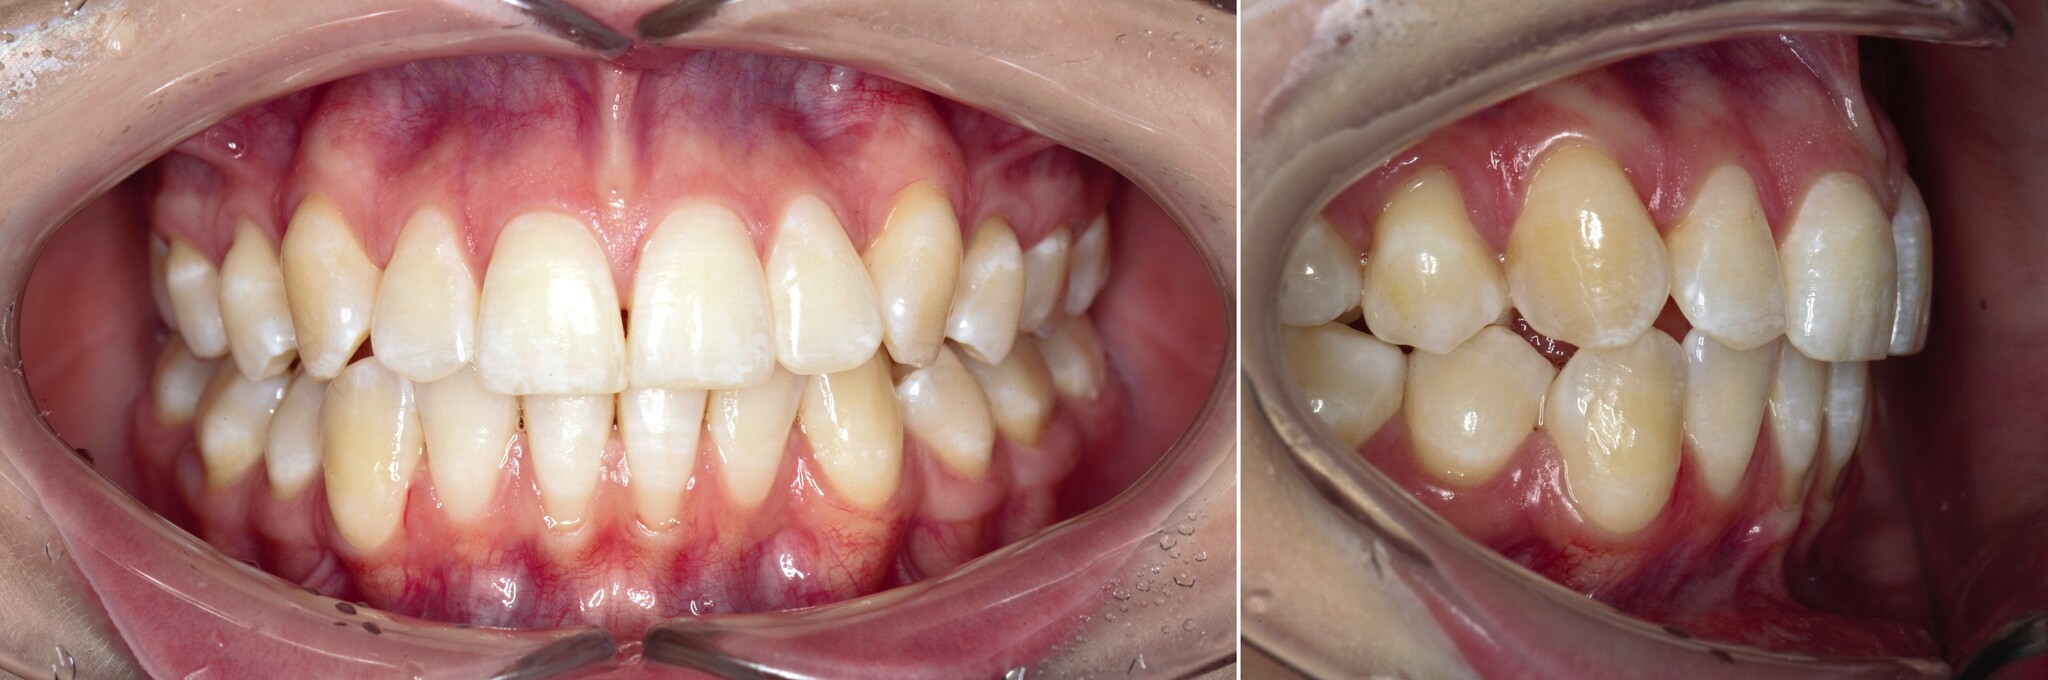

После снятия швов через несколько месяцев область операции выглядит так:

Рубец будет потихоньку разглаживаться.

Сравним:

Вот так и выглядит операция – вестибулопластика.